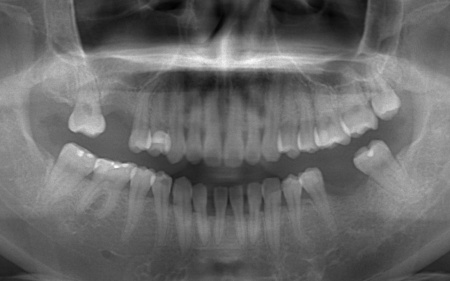

拝見したところ、右上と左下の奥歯に強い痛みが出ていました。

レントゲンで確認した結果、どちらも歯の根が割れていることが判明しました。

また、上下の歯を噛み合わせた際に前歯が噛み合わず隙間ができる開咬(かいこう)と呼ばれる噛み合わせも見られました。

開咬は奥歯に負担が集中しやすく、その影響で今回のように歯の根が割れてしまった可能性が高いと考えられます。